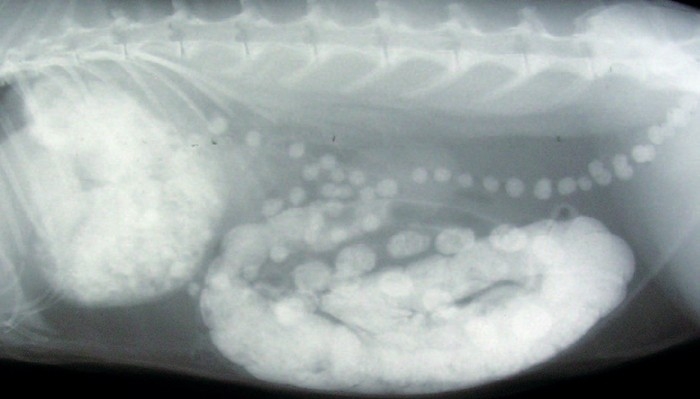

Lateral abdominal radiograph approximately six hours after administering barium orally. Barium is obvious within the stomach, caecum and colon. Faecal pellets containing barium are also present.